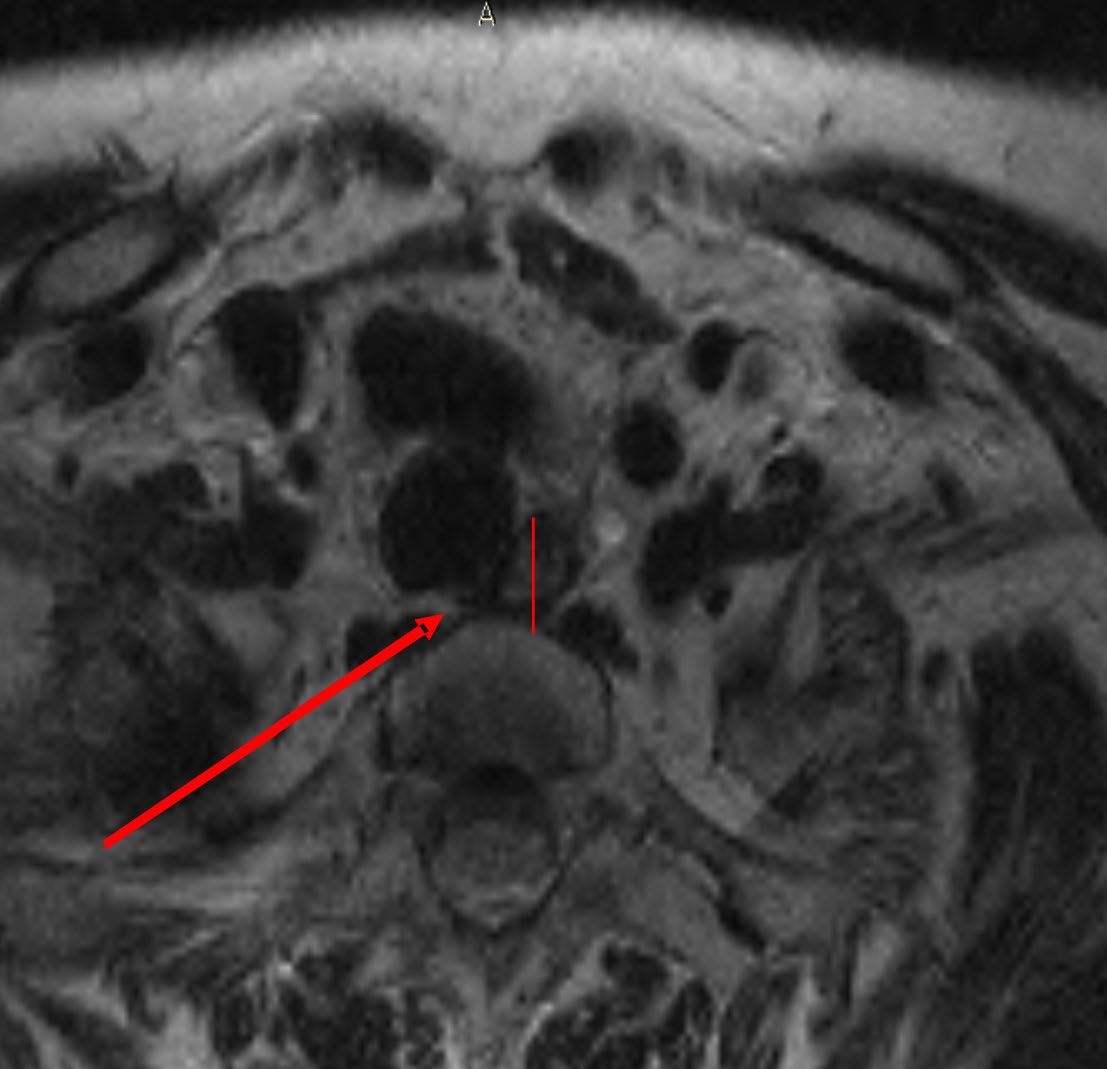

Оценка томографических срезов через 12 месяцев после хирургического вмешательства позволила определить изменение формы просвета пищевода за счет увеличения его переднезаднего размера и перемещение органа к левой боковой стенке трахеи (рис. 2).

Рис. 2. Пациент К., 44 года. Диагноз: многоузловой коллоидный зоб, эутиреоз. Объем щитовидной железы 173 см3. Состояние через 12 месяцев после тиреоидэктомии. Расположение пищевода у левой боковой стенки трахеи. Увеличение переднезаднего размера пищевода

Просвет пищевода в послеоперационном периоде увеличивался в переднезаднем направлении. Дооперационная медиана этого параметра составляла 0,37 см. Через два месяца после тиреоидэктомии он также соответствовал дооперационным значениям. Однако через шесть месяцев после хирургического вмешательства наблюдали его увеличение в среднем на 1,3 см. Через шесть месяцев медиана переднезаднего размера органа увеличилась в 4 раза, через 12 месяцев – в 6 раз, что достоверно превышает дооперационные значения (Т-критерий Вилкоксона, p ≤ 0,01). Орган приобрел шаровидную форму (табл. 1).

Одновременно с расширением пищевода происходило его смещение к левой боковой стенке трахеи. До операции медиана смещения относительно вертикальной оси составляла 0,32 см. Через два месяца после операции она возросла до 0,41 см, через шесть месяцев – до 1,1 см, а через 12 месяцев – до 2,12 см. Смещение пищевода по горизонтальной оси влево наблюдали со второго месяца послеоперационного периода, и в 73 % случаев пищевод через год после тиреоидэктомии располагался параллельно трахее (табл. 2, 3).